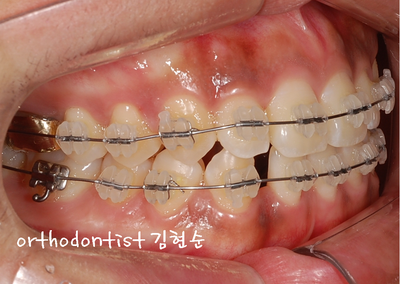

- 화살표 좌/우 방향 공간 확보 후 inplant

- 교정 후 개선된 치아 중심선입니다

- implant 식립 후 개선된 치열 옆모습입니다

- 상 / 하 모두 교정 후 가지런한 모습으로 마무리되었습니다

-

처음보다 달라진 이미지가 보여지며 밝은 미소 또한 갖게 되었습니다